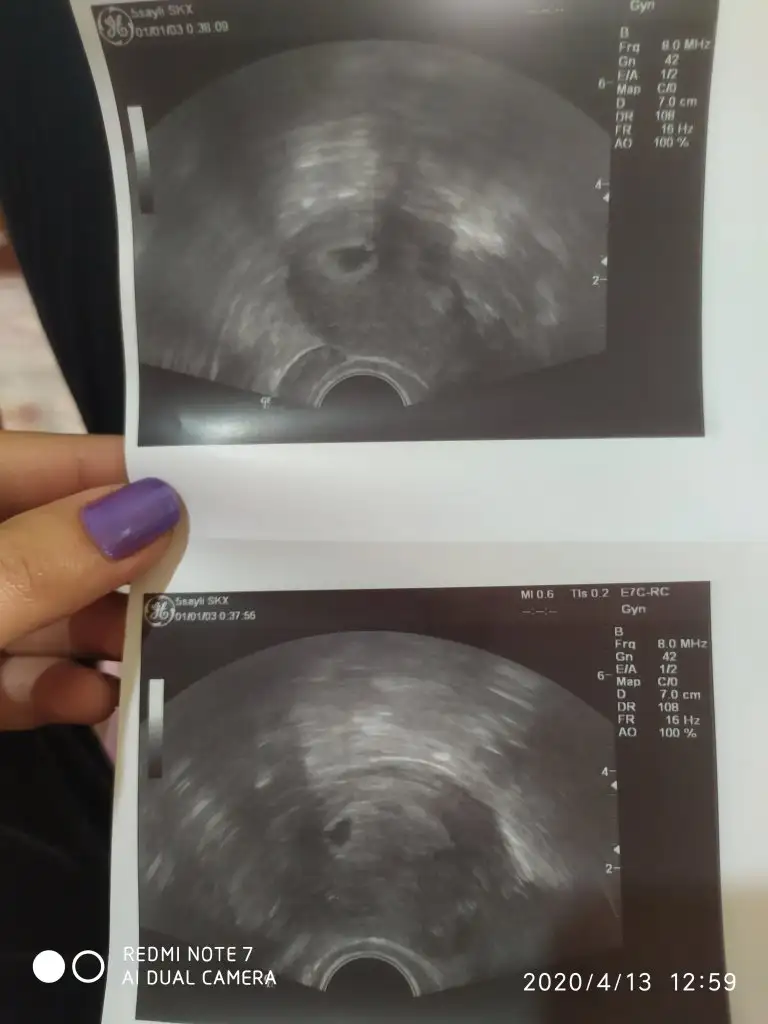

Çok az büyütebiliyorum, yakınlaştırmıyor çok. Kese bu attığın. Sağ taraftaki hareketli kısımda da yolk sac denilen 2. Kese gibi bişey ve bebek oluşacak yüksek ihtimalle.![]()

Ikitanemi kese var canim altlı ustlu yoksa tek keseyimi ikitane cikartmis doktorEki Görüntüle 2619019 boyle gozuktu bebekmi kesemi bilmiyorum

masallah canim kese buEki Görüntüle 2619019 boyle gozuktu bebekmi kesemi bilmiyorum

Iki tane fotoyumu diyorsun yoksa fotolarda gozuken iki tane seyiIkitanemi kese var canim altlı ustlu yoksa tek keseyimi ikitane cikartmis doktor

Tektir canım bizim doktor da aynı keseyi 2 kağıda basmıştı böyle. Bir görüntü daha yakındı mm görünüyordu diğeri uzaydaki görünüş gibiydi.Ikitanemi kese var canim altlı ustlu yoksa tek keseyimi ikitane cikartmis doktor

Iki fotodakilerde ayni ehrhlse biri yakin biri uzak cekmis ikitanemi kese var tek.mi kese canımIki tane fotoyumu diyorsun yoksa fotolarda gozuken iki tane seyi

Iki fotodakilerde ayni ehrhlse biri yakin biri uzak cekmis ikitanemi kese var tek.mi kese canım